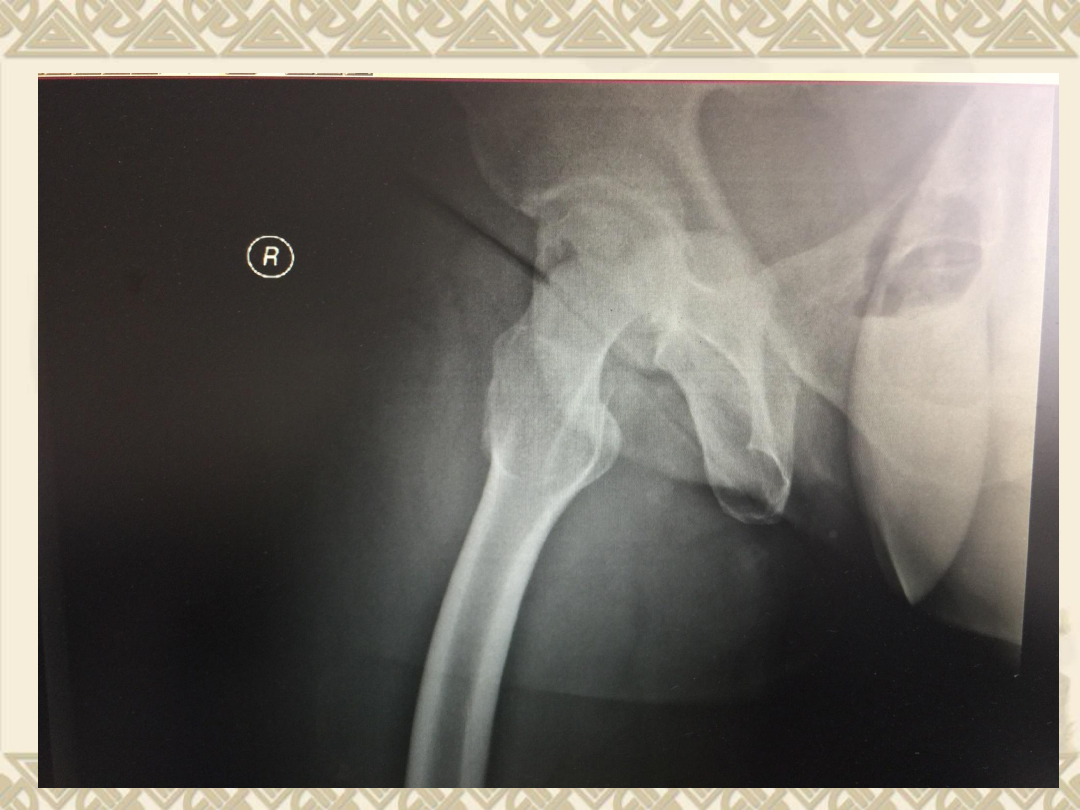

入院后拍片

v

1

、右股骨头骨折(

Pipkin

Ⅳ型骨折)

2

、髋关节后脱位

3

、髋臼后缘骨折